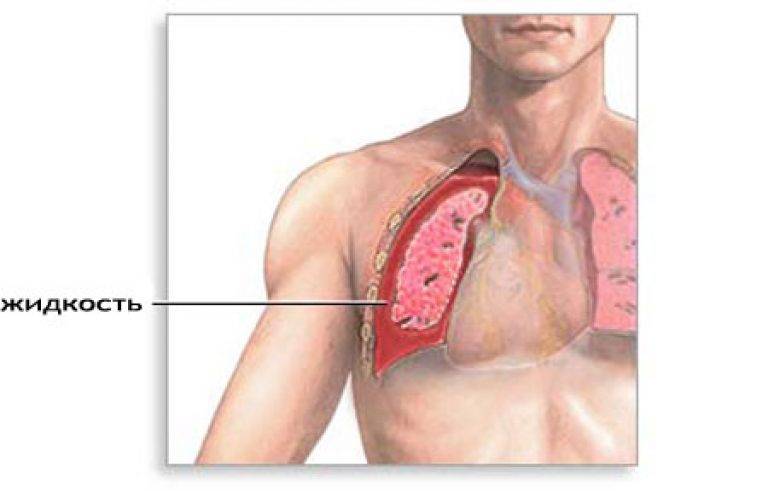

Симптомы и причины скопления воды в легких